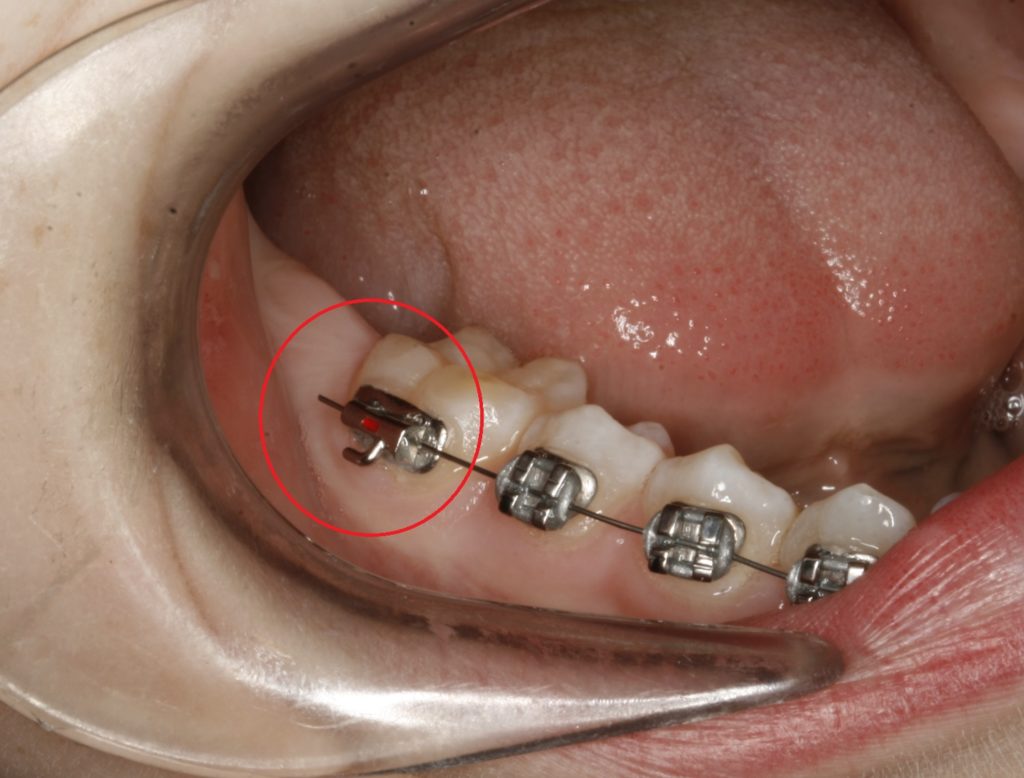

Dersom du er uheldig og reguleringsstrengen stikker ut mot kinnet og irriterer/lager gnagsår, kan du prøve å klippe den lange delen med en avbiter. Bruk den flate delen av avbiteren/saksen mot klossen, slik du ser på bildet nedenfor.